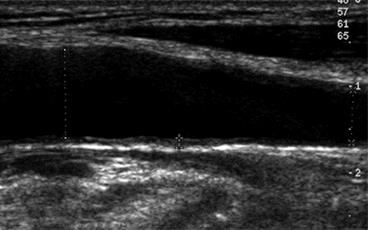

Сосуды. УЗИ сонных артерий проводят в тех случаях, когда целесообразно выявление гипертрофии стенки сосудов или бессимптомного атеросклероза. При УЗИ брахиоцефальных артерий необходимо определить толщину комплекса «интима-медиа» и наличие атеросклеротических бляшек.

В норме у артерий среднего калибра мышечного типа ширина «интима-медиа» не более 0,9 мм. Кроме эндотелия, они состоят из очень узкого слоя неорганизованных соединительнотканных клеток, происходящих большей частью из медиа. Внутренняя эластическая мембрана высокоорганизована, имеет поры для прохождения в медиа питательных веществ, состоит из ГМК с ретикулами коллагена и эластических волокон. ГМК обладают свойством сократимости за счет волокон актина и миозина. Функция первых заключается в вазодилатации и вазоконстрикции (в зависимости от типа стимула), синтезе различных типов коллагена и эластина, компонентов экстрацеллюлярного матрикса (протеогликанов), стимуляторов роста и цитокинов. Медиа разделена эластической внешней мембраной, в которой возможно наблюдать нервные окончания.

Увеличение толщины комплекса «интима-медиа» является не только следствием развития атеросклеротического процесса, но и ответом на увеличение потока и напряжения артериальной стенки при артериальной гипертензии, что может приводить к ремоделированию артерии.

Ремоделирование стенки общей сонной артерии. ТИМ ОСА = 0,11 см; диаметр ОСА в средней трети = 0,61; диаметр ОСА в дистальной трети = 1,02 см.